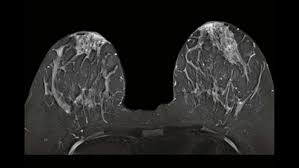

- Breast MRI Images

The images produced by a breast MRI are very detailed and can show the following:

Tumors or Growths: MRI can detect small tumors, often even those that are too small to be seen on a mammogram or ultrasound.

Breast Tissue Density: MRI provides a clearer view of dense breast tissue, which can make it difficult for other imaging methods to identify abnormalities.

Extent of Cancer: If cancer is found, MRI aids doctors in determining the size, location, and extent of the tumor(s) in the breast, including determining if the cancer has spread to nearby lymph nodes or other areas.